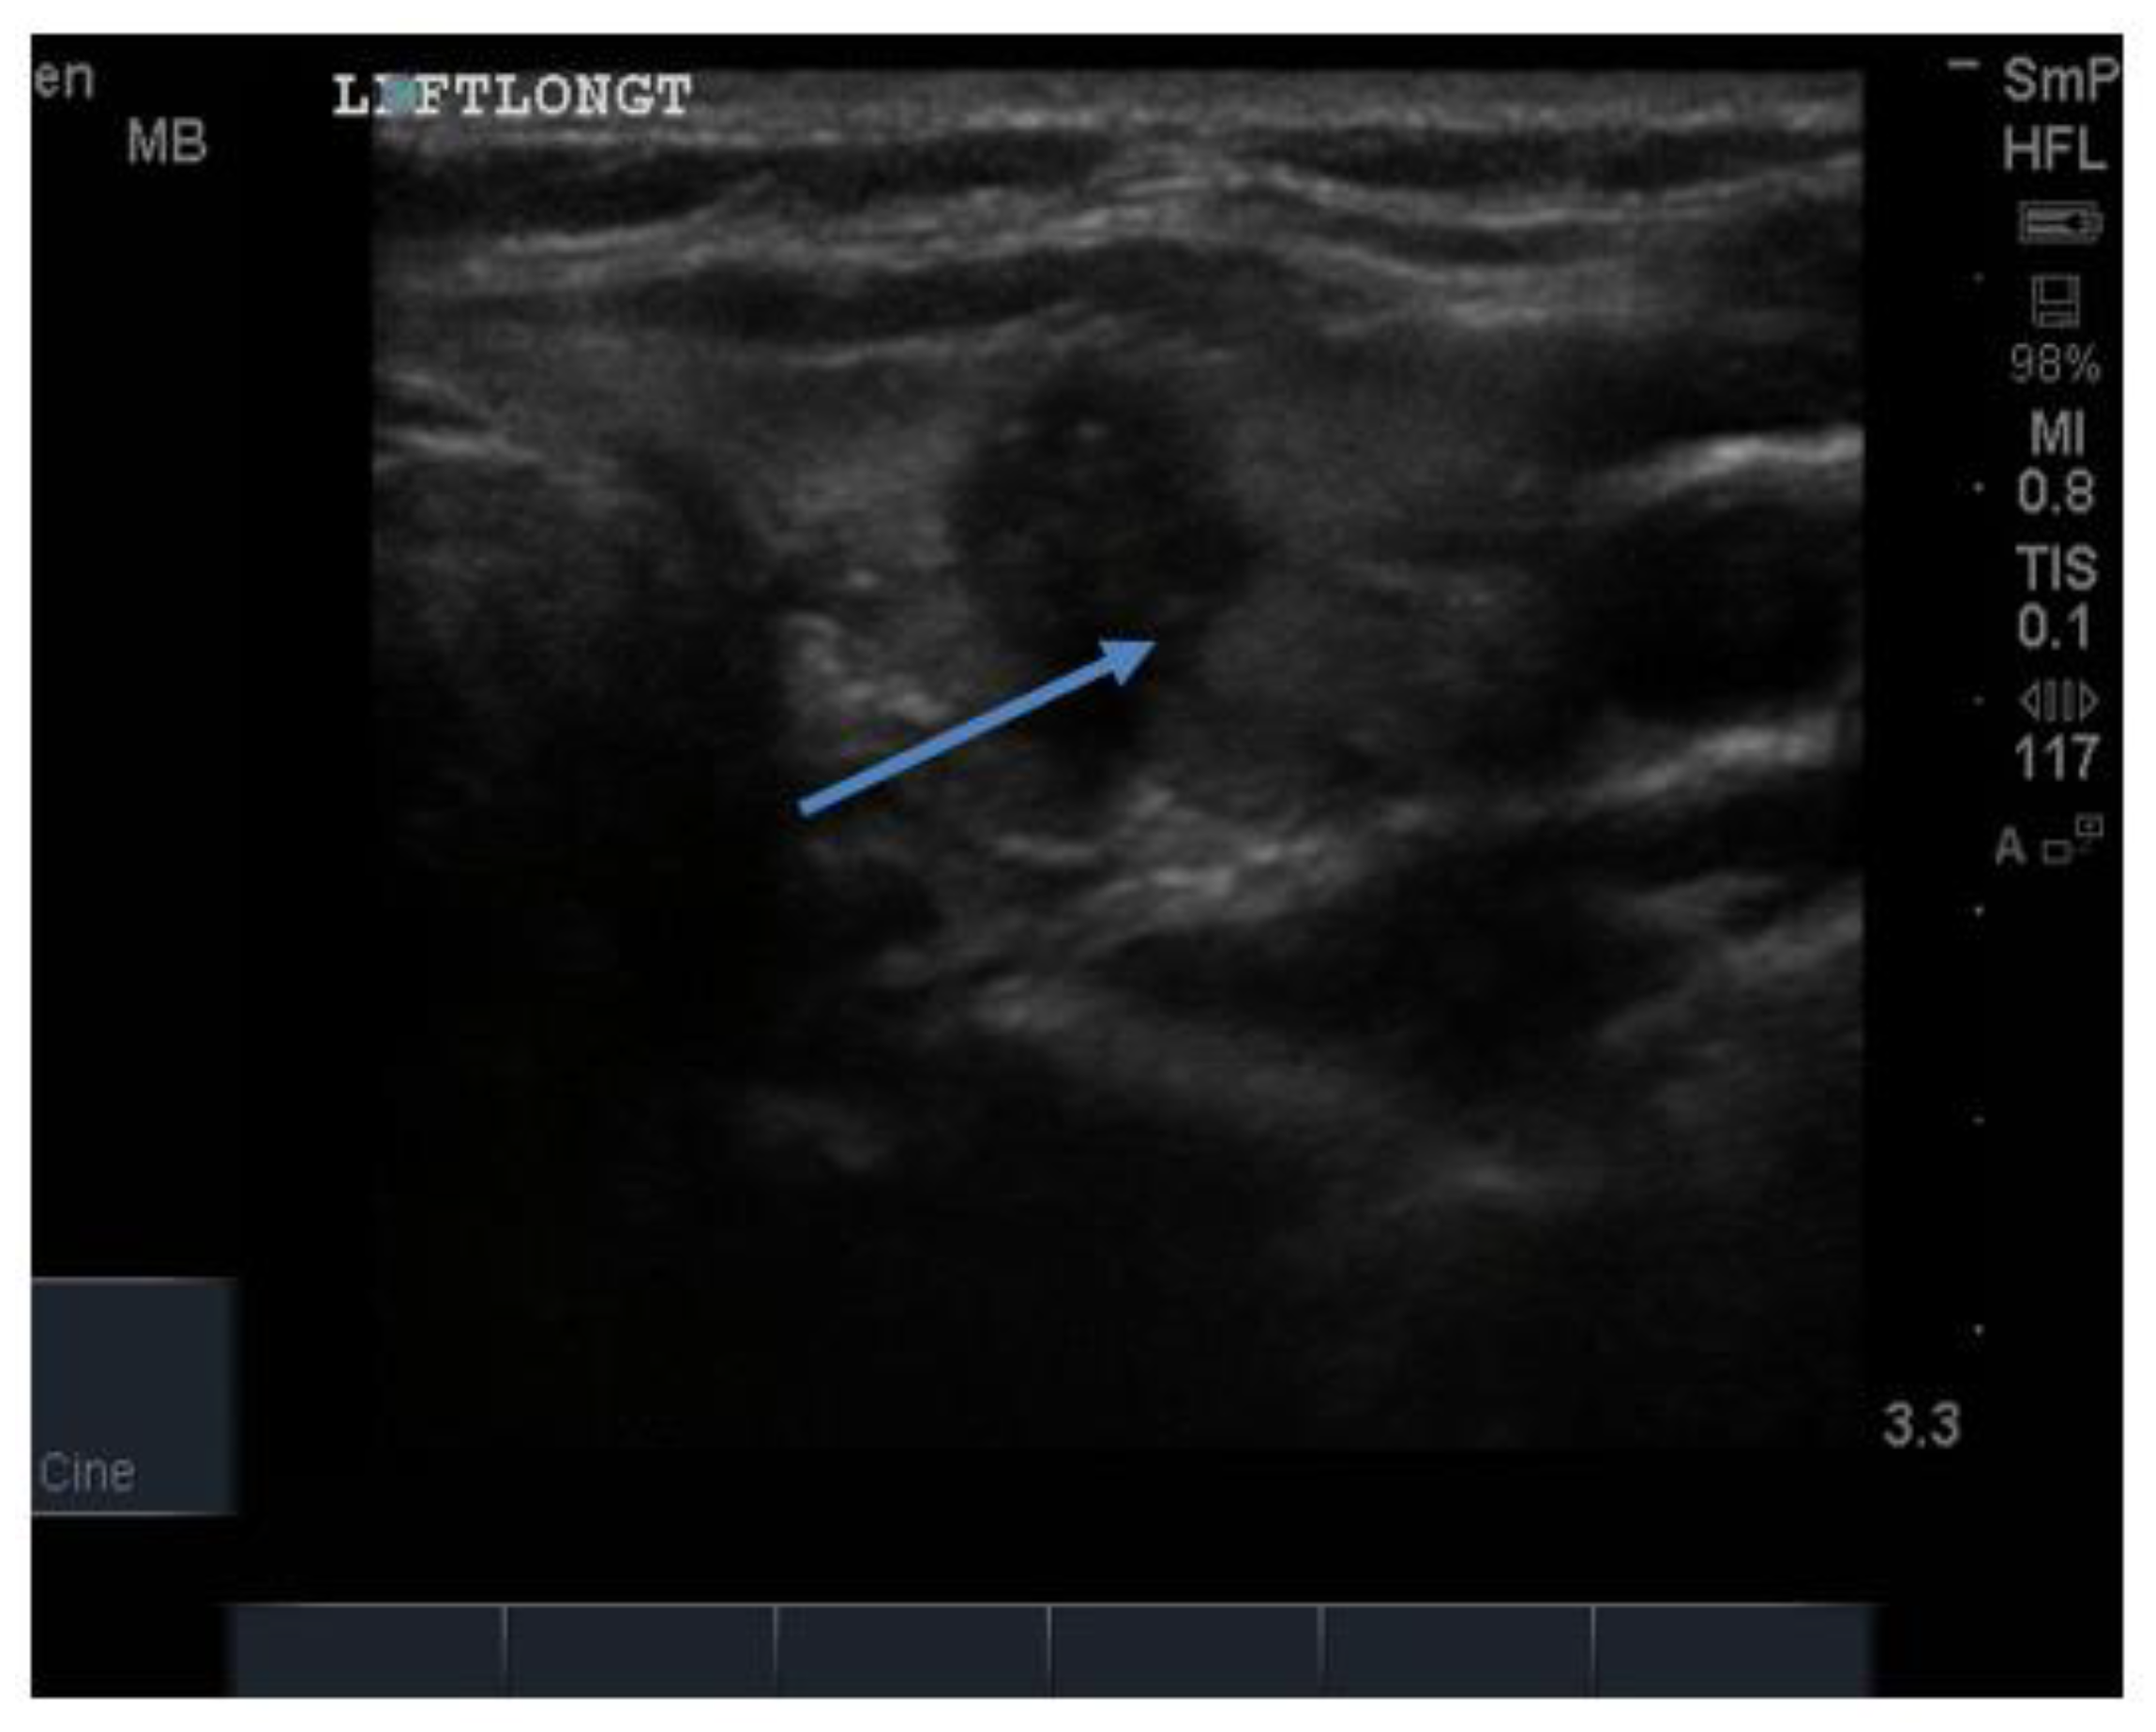

The blood supply in typical Graves’ disease is diffusely increased (and associated with a murmur), sometime up to 100 times normal, and the gland texture on ultrasound is usually heterogeneous (patchy) with a fine cystic appearance throughout, which reflects the diffuse nature of the inflammatory process (Figure 15). Following radio iodine treatment, the normal gland architecture is disrupted because the follicles are destroyed, and scar tissue predominates.

Figure 15.

Thyroid ultrasound from two patients with Graves’ hyperthyroidism. In (A) is shown an example of early Graves’ hyperthyroidism manifest as multiple small inflammatory and lymphoid lesions, often described by the consultant radiologist as “nodules” blue arrow. In (B) is shown an enlarged thyroid, with a thick isthmus and a generalized patchy hypo echoicity due to the lymphocytic inflammation and thyroid cell proliferation. In (C) is shown the increased vascularity in the thyroid of the patient shown in (B).